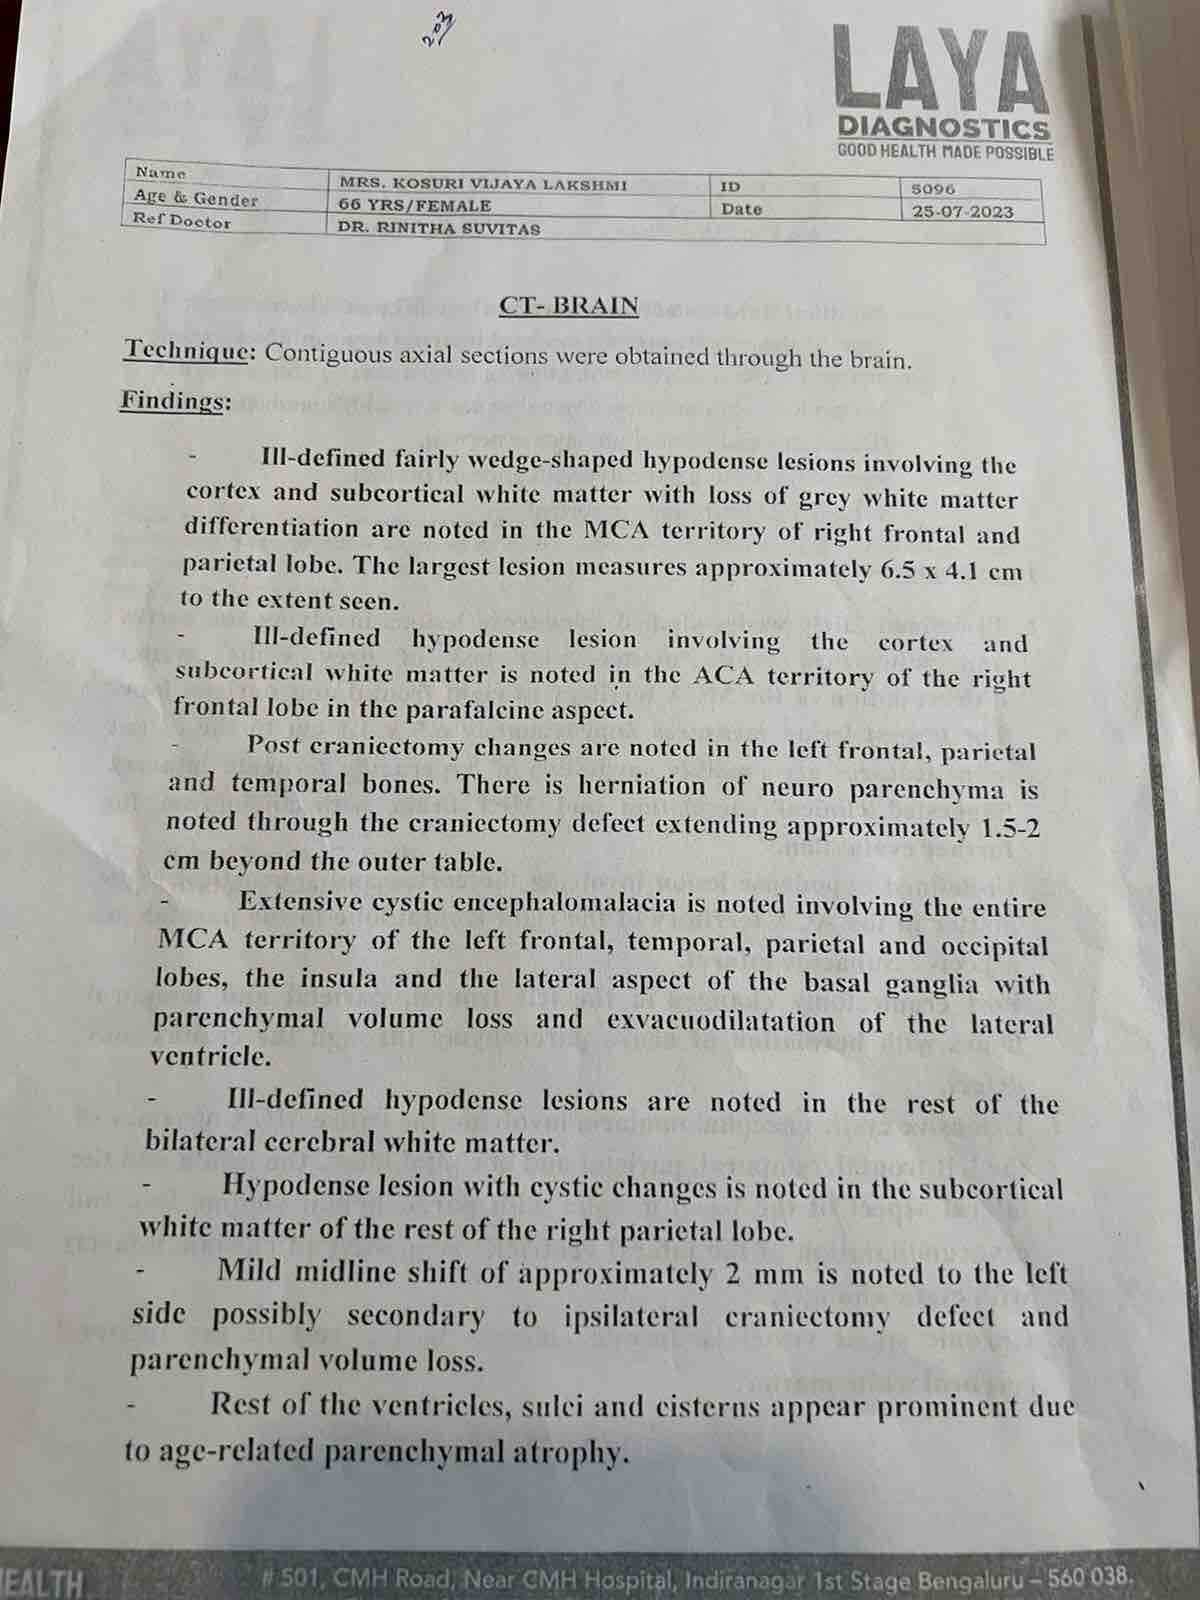

We are reaching out to you today with a heavy heart and a plea for help. Our beloved 66-year-old mother K VIJYA LAKSHMI, has been facing an incredibly challenging journey since 16th May when she had brain stroke & underwent emergency brain and abdomen surgery. Her recovery has been a rollercoaster of ups and downs.

During her hospitalization, she endured multiple complications, including respiratory distress, recurrent severe infections, and even seizure-like activity. Through it all, she has shown immense strength and determination. Still she require three more surgeries to stand on the path of recovery.